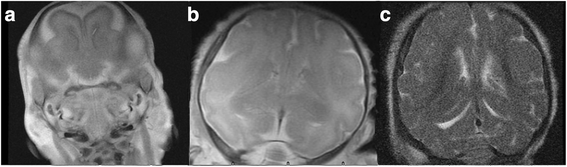

The measuring method was the size of the ROI at a point region of 1 mm2, which was moved within the anatomical position to obtain the highest FA value. The selected ROIs included deep cerebral WM including the anterior limb internal capsule (ALIC), the posterior limb internal capsule (PLIC), the genu corporis callosi (GCC), the splenium corporis callosi (SCC), the periventricular white matter (PV), the optic radiation (OR), the corona radiate (CR), and the superficial white matter regions including the frontal lobe (FL), temporal lobe (TL), parietal lobe (PL), and occipital lobe (OL), as shown in Fig. 1. Measurements were of both sides of the brain.

Fetal brain graph of interest region (from 1 to 12 were the corona radiate, parietal lobe white matter, frontal lobe white matter, occipital lobe white matter, corpus callosum genu, periventricular white matter, the anterior limb internal capsule, white matter of temporal lobe, optic radiation). (a) the level of semioval center (b) the level of lateral ventricle (c) the level of basal nuclei